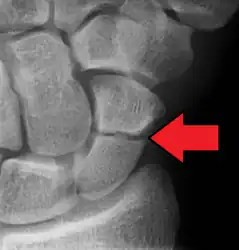

A more obvious scaphoid fracture on a scaphoid view X ray